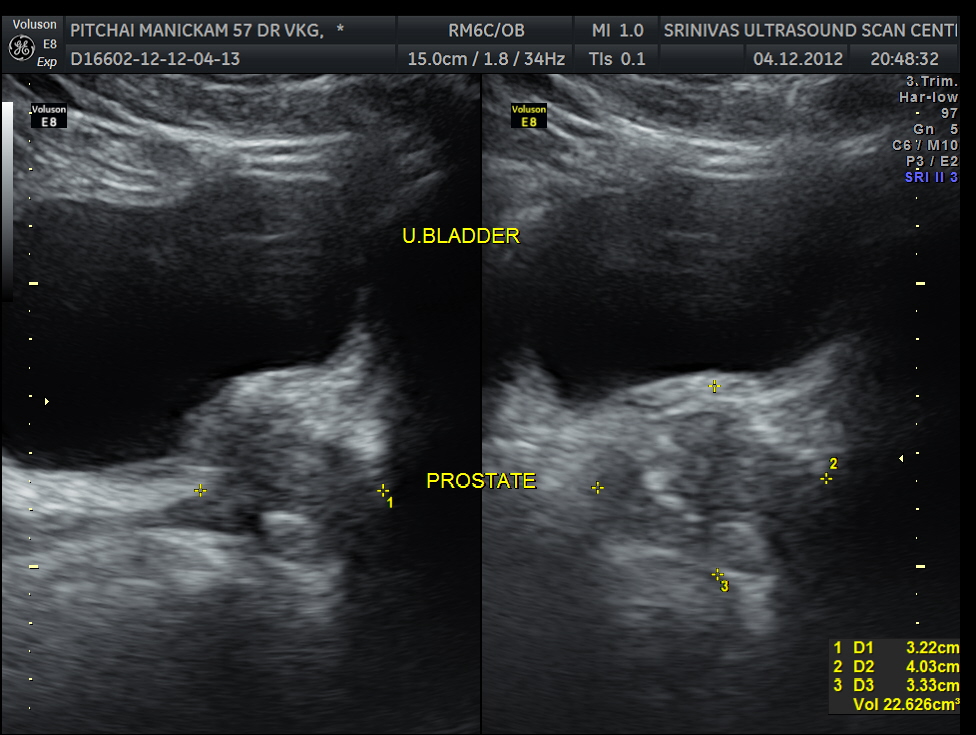

Liver, gall bladder , pancreas, spleen and the left kidney were normal . The prostate showed mild enlargement.